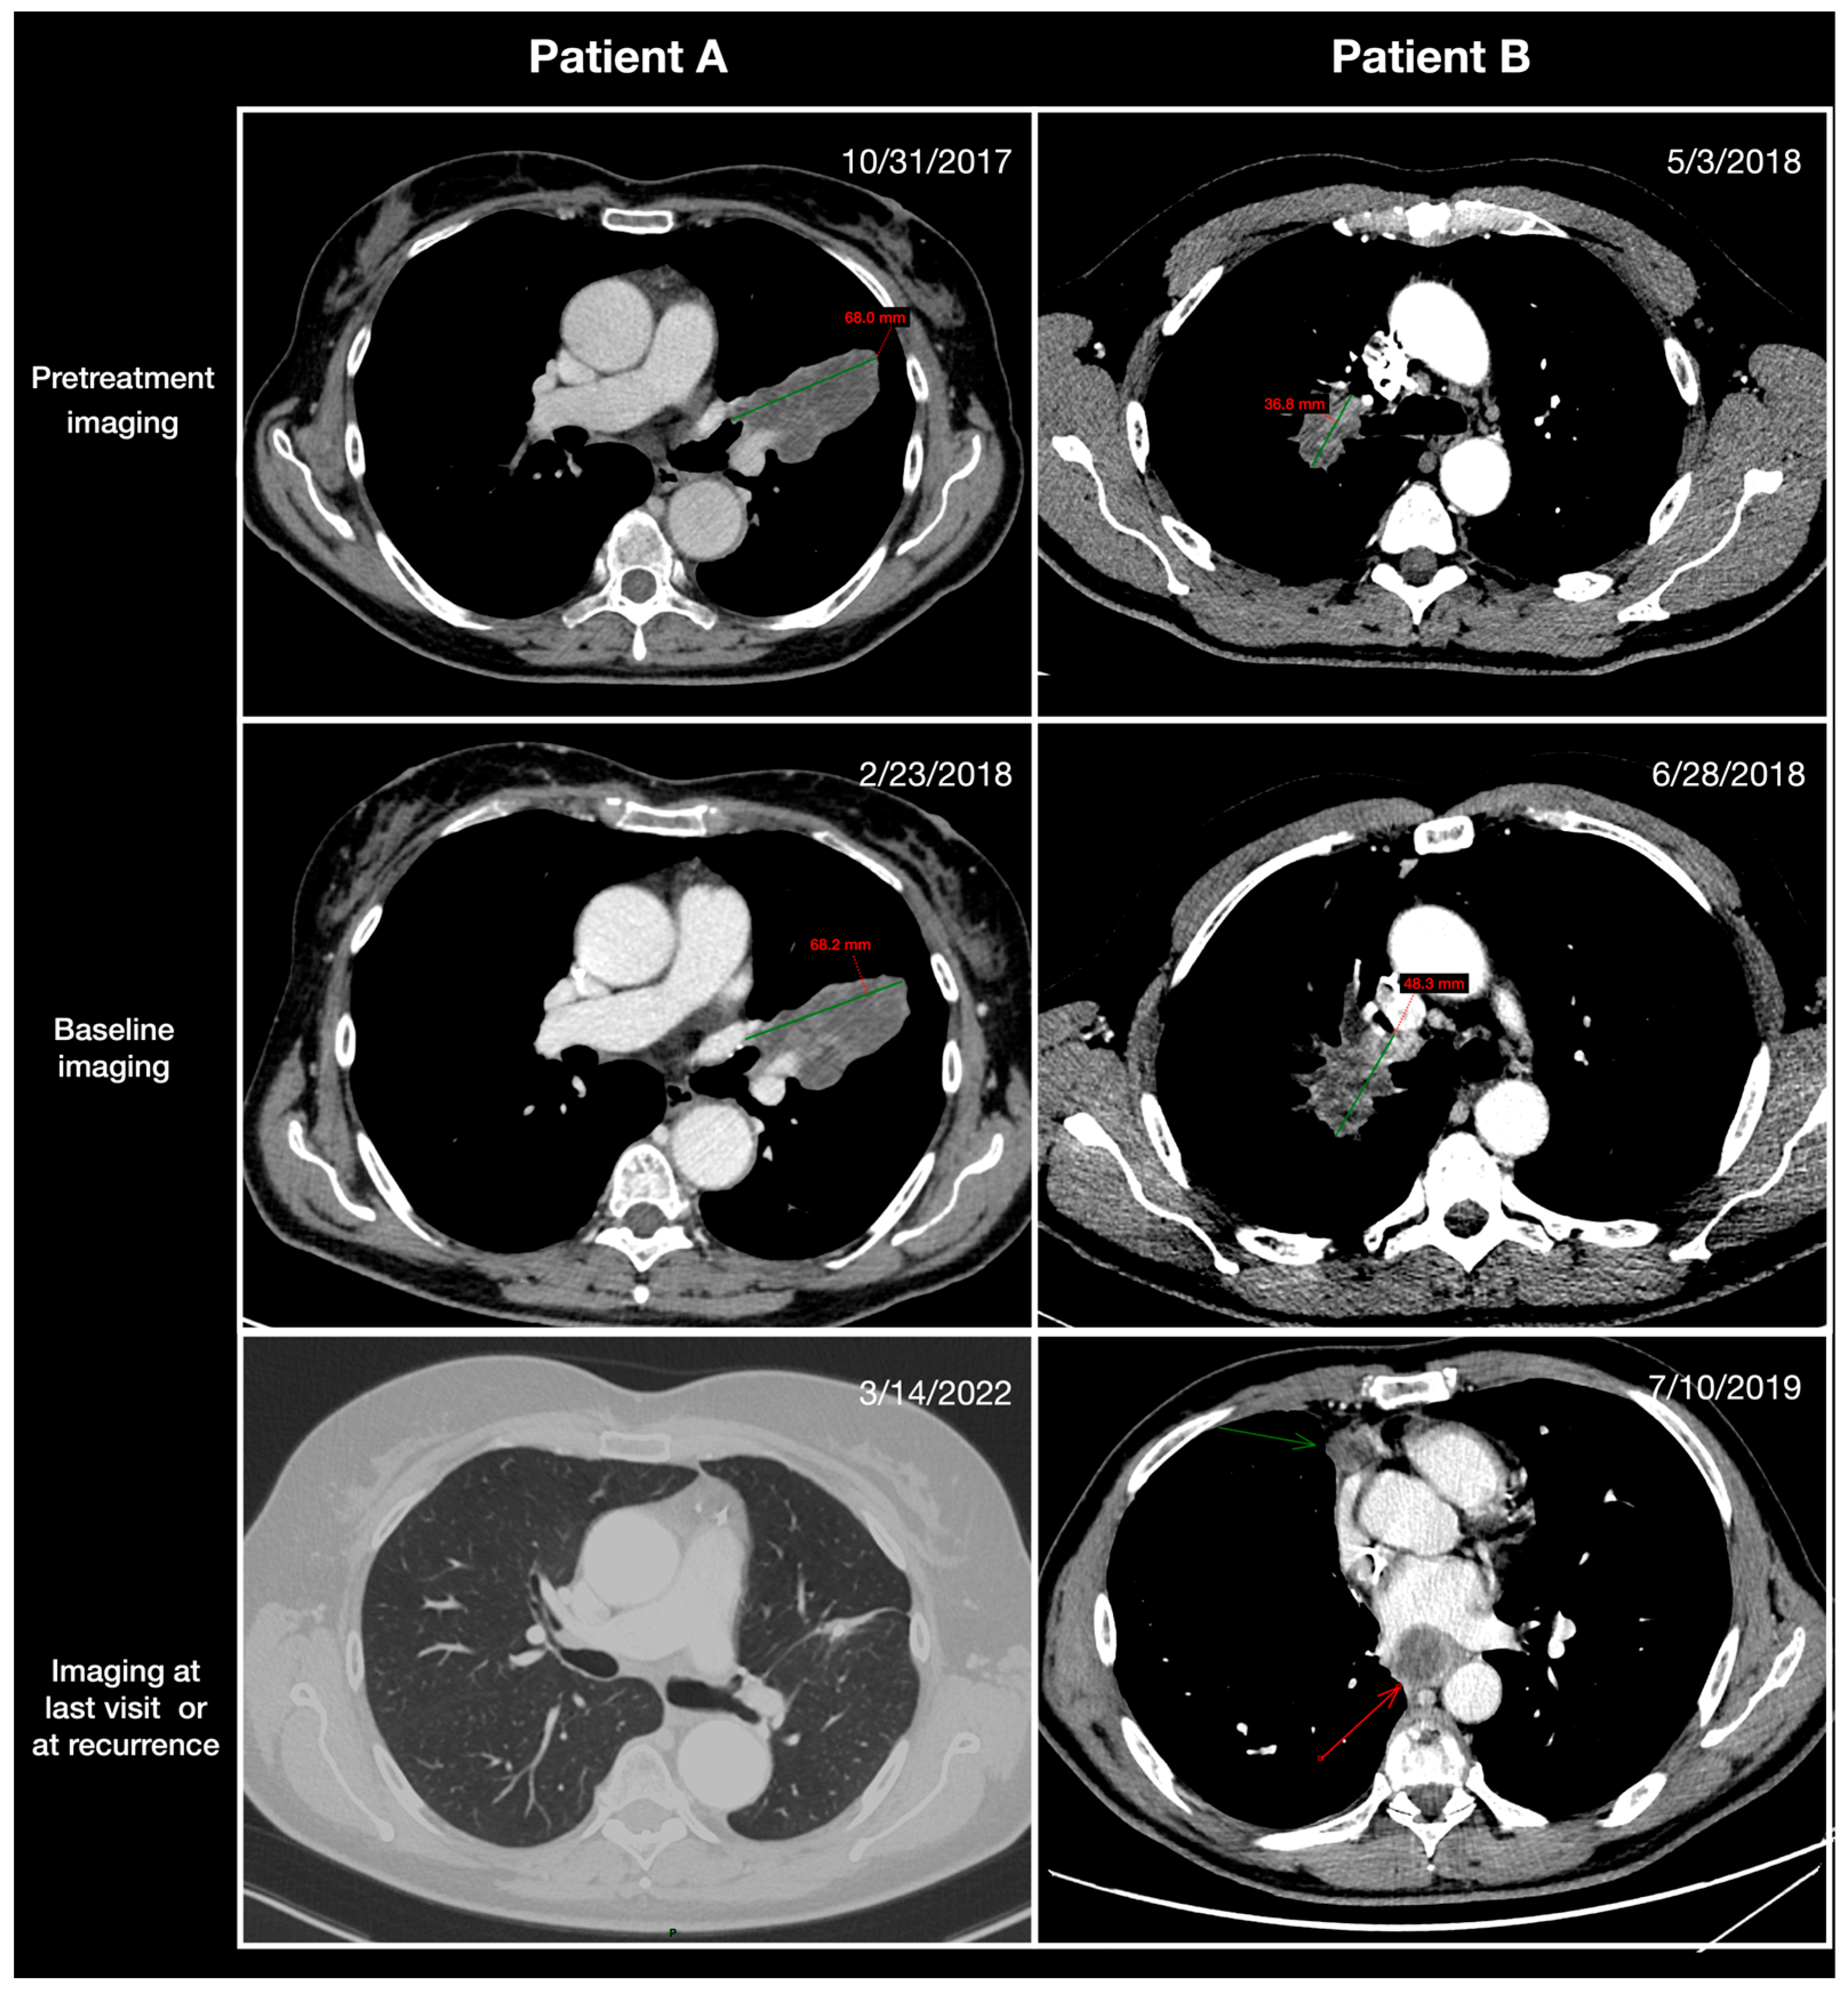

2.2. Radiological Assessment